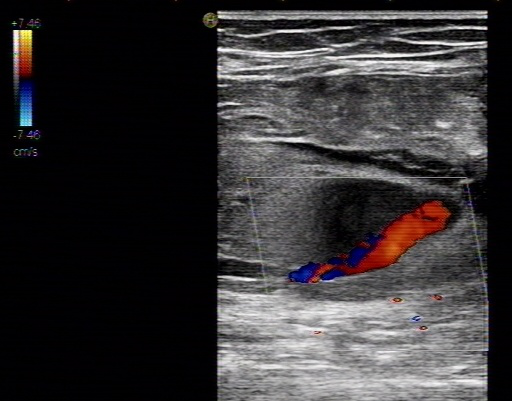

血流呈花色渦流,仔細(xì)掃查,為腹主動(dòng)脈的局部膨大,動(dòng)脈管壁完整,腔內(nèi)低回 聲考慮為血栓形成,超聲提示:真性動(dòng)脈瘤伴血栓形成。